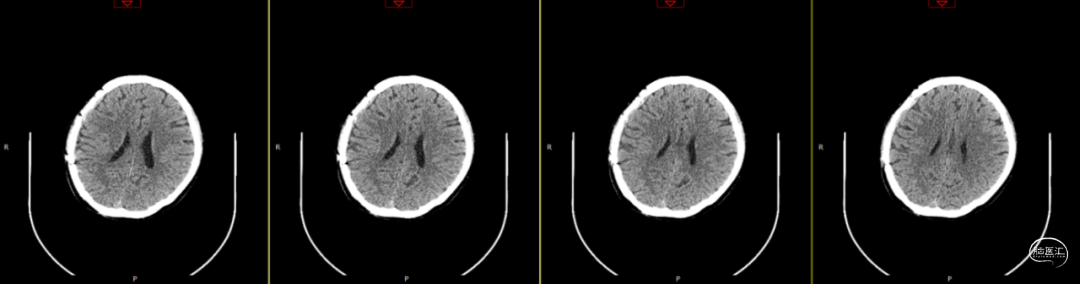

第1次术后88天,即第2次入院前1天复查(如上图),经反复沟通病情,病人及家属仍拒绝去除骨瓣清创手术,但同意进行手术清创。术中见右侧额部皮下炎性肉芽组织增生,伴有少量分泌物流出,骨瓣下见乳白色脓性分泌物,未闻及明显异味,收集脓性液体送细菌培养、涂片检查,局部硬膜增厚,较多炎性增生组织于局部硬脑膜黏连紧密,缓慢刮除局部异常增生组织后,低功率双极电凝行硬脑膜止血,骨瓣可见右侧额部外板局部被侵蚀,清理表面异物后,使用双氧水浸泡冲洗,并浸入碘伏液中消毒;彻底清除硬膜外、骨缘及右侧额部皮下增生异常组织,额顶部愈合不良刀口予以局部清创,反复使用双氧水及稀释后碘伏溶液冲洗创面,更换钛板及钛钉,还纳骨瓣并固定,皮下留置负压引流管1根,缝合逐层。术后使用万古霉素静脉抗炎治疗,留取术中脓性分泌物进行细菌培养及涂片检查(培养及检验均呈阴性)。

第2次术后第1天复查颅脑CT资料(第1次术后92天)(如上图)。